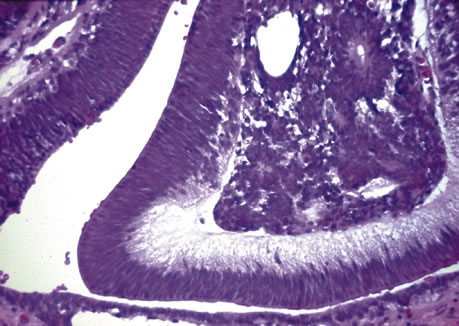

Persistent hyperplastic primary itreous (PHPV) is usually a unilateral condition that leads to fibrovascular connections in the retrolental area. These connections may reach the posterior retina and cause a severe tractional detachment. Adipose tissue, cartilage, and smooth muscle may be seen in the retrolental mass. Ciliary processes are stretched or elongated as well.49–54 A group of disorders characterized by trisomy 13-15 may also demonstrate the elongated ciliary processes and retrolental findings seen in PHPV.55–57 This condition (also termed Patau's syndrome) demonstrates retinal dysplasia and rosette-like configurations of the retina.